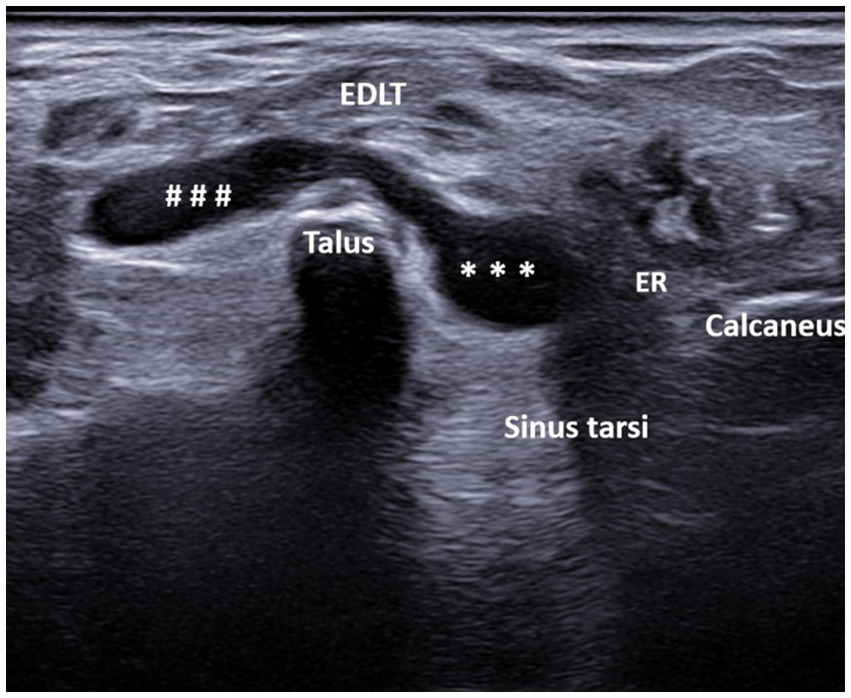

Figure 3

A 44-year-old patient with spondyloarthritis. Ultrasound image showing bilocular GB with the transducer positioned in the short axis of the foot (left side is medial). The transverse ultrasound image of the dorsolateral ankle reveals a bi-lobed, anechoic fluid collection (* – lateral lobe, # – medial lobe) between the extensor digitorum longus tendon (EDLT) and the talus. ER, extensor retinaculum and EDLT, extensor digitorum longus tendon.

A total of 608 patients underwent ultrasound examination for foot and/or ankle pain in our department from 1 July 2022 to 31 December 2023. Of these 608 patients, the search based on the previously cited keywords identified 76 patients who met the inclusion criteria. After reviewing the images of these patients, 13 were excluded for the following reasons: fluid collection was seen only deep within the sinus tarsi without spreading above the dorsolateral talar contour and beneath the EDLT (3 patients), tenosynovitis of the EDLT was diagnosed (6 patients), or no fluid was actually seen (4 patients). Thus, the final study group consisted of 63 patients with different primary rheumatic diagnoses (Table 1). Of these, the finding was unilateral in 48 patients and bilateral in 15 patients, resulting in a total of 78 bursae analyzed. Of the 63 patients, 45 (71%) were women and 18 (29%) were men. The average age of the patients was 61.7 years (range: 25–85 years). The right foot was affected in 55% (44/78) of the cases, and the left foot was affected in 45% (34/78) of the cases. The fluid collection extended from the sinus tarsi, along and beneath the inferior extensor retinaculum, reaching the space between the EDLT and the dorsolateral surface of the head of the talus. The large bursae also extended medially from this space. The bursae were predominantly unilocular (49/78) rather than multilocular (29/78). In all cases, the epicenter of the fluid collection was situated in the plane between the EDLT and the dorsolateral talar contour (Figure 2, Supplementary Video 1). When present, the second loculus was located medially to the main loculus and positioned over the talus (Figure 3). The majority of the fluid collections were clearly anechoic (69/78) (Figures 2, 4). In the remaining cases, internal hyperechoic foci were observed (Figure 5), making the content heteroechoic, and an internal septum was present in one case.